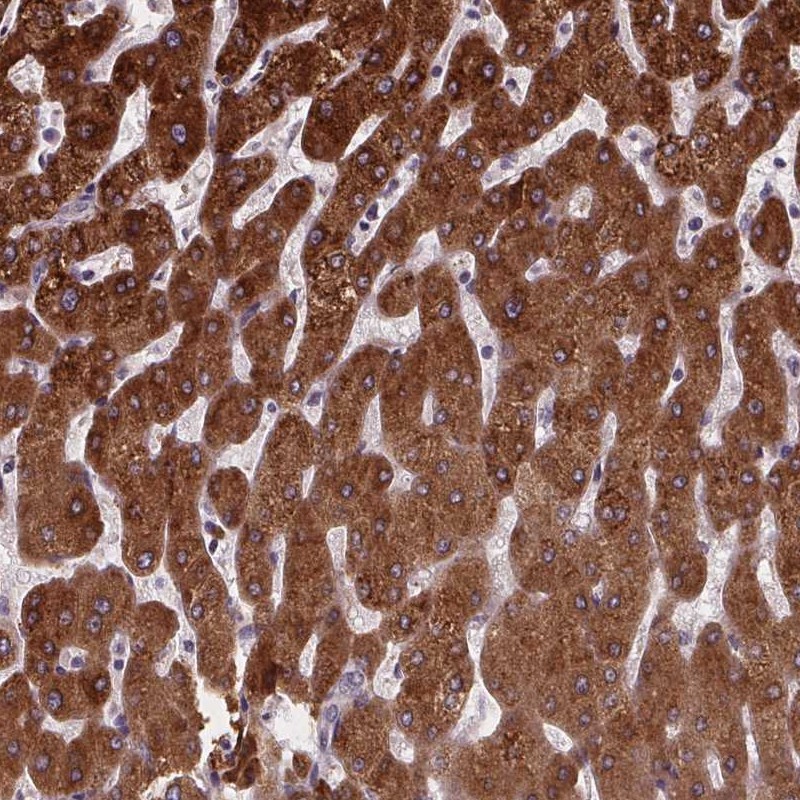

Immunohistochemical staining of human liver shows strong cytoplasmic positivity in hepatocytes.